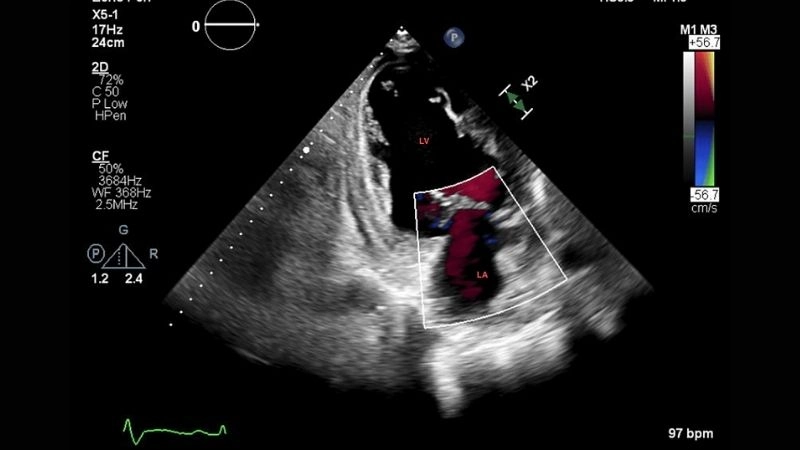

Images visual examples of Left Ventricular Non-compaction Cardiomyopathy

This abnormal structure weakens heart function, disrupts blood circulation, and can lead to life-threatening complications if not diagnosed early.